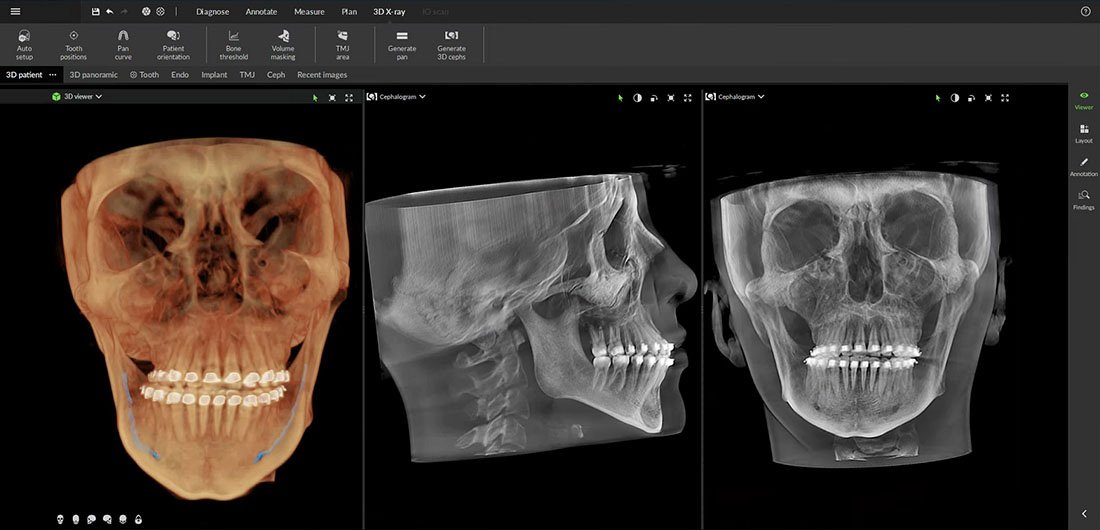

A Cone Beam CT, vagyis a CBCT jelentése kúpnyalábos komputertomográfia, ami egy nem invazív képalkotási technikát jelöl a fogászatban. Az eljárás során a CT-készülék egy kúpalakban szétterülő röntgensugárnyalábbal kétdimenziós képek sorozatát készíti el a páciens feje körül különböző szögekből. Ezeket a képeket rekonstruálják, hogy létrehozzák a száj- és állkapocs-struktúrák háromdimenziós képét, beleértve a fogakat, a csontot, az idegeket és a lágyszöveteket. Ez az átfogó vizualizáció lehetővé teszi a fogorvos számára a pontosabb diagnózis felállítását, illetve a kezelés precíz megtervezését.

A hagyományos panorámafelvételeken képi torzulások jelentkezhetnek, amelyek megnehezíthetik a röntgenfelvételek kiértékelését. A fogászati CT-gép viszont méretarányos, torzítás nélküli, több irányból megjeleníthető 3 dimenziós képet készít, segítségével ráadásul nemcsak a csont mennyiségére, hanem a minőségére is fény derül. A CBCT emellett alacsonyabb sugárterhelést jelent a páciens számára, mivel ezek a készülékek nem exponálnak folyamatosan, mint a hagyományos CT-k, így a CBCT csupán minimális sugárdózissal terheli a pácienst.

Ez az új képalkotási eljárás lehetővé teszi, hogy a vizsgálandó területről 1:1 méretarányos, rávetülés nélküli, több irányból megjeleníthető 3 dimenziós kép készüljön. Ezenkívül nemcsak a csont mennyisége, hanem a csont mínősége is vizsgálható a felvételeken.

A 3D technológiára épülő multimodalitású képalkotó platform lehetőségei a fogászati felvételi igények teljes spektrumát lefedik, az endodontiától a legösszetettebb implantációs esetekig.

Komplex sebészeti műtétek előtt egyértelmű és pontos adatokkal segít meghatározni a csont minőségét és méretét, az anatómiai struktúrákat, így a műtét a lehető legpontosabban tervezhető és kivitelezhető.

A fogszabályozási kezelések értékelése is egyértelműbb a nagy felbontású CBCT képalkotással. Összetett esetek diagnosztizálását segíti a DEXIS OP 3D LX a számfeletti vagy ki nem tört fogak legpontosabb pozicionálásával.

A temporomandibuláris ízület bilaterális vizualizációjára, a keményszövet degeneratív elváltozásainak felmérésére és az okklúzió pozicionálására is alkalmas, melyek mind támogatják a gnatológiai, azaz állkapocsízületi diagnózist és kezelést.